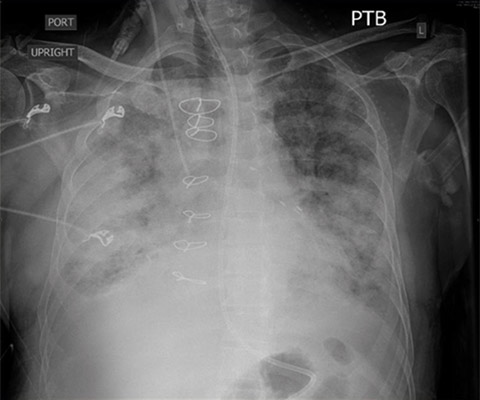

Given his renal failure and anticipated limitations to aggressive diuresis with medical therapy, arrangements were made to emergently intubate the patient, augment ionotropic support, escalate diuresis attempts with diuretics while calling the family to discuss care options including likely need for dialysis. As the patient was being prepped for intubation, X-ray imaging was obtained confirming the diagnosis of pulmonary edema. By then, though, the patient had already been given aggressive diuretic therapy, received escalating ionotropic support, bronchoscopy was set up at the bedside for endobronchial evaluation after the intubation given his fevers, and the family had been notified. POCUS with a small, extremely portable device had allowed for convenient and rapid evaluation, diagnosis, and intervention in a complex patient. A repeat chest X-ray just one hour after intubation showed marked improvement in the patient’s pulmonary edema.Clinical impact

CXR pre-intubation showing diffuse bilateral alveolar and interstitial pulmonary edema.